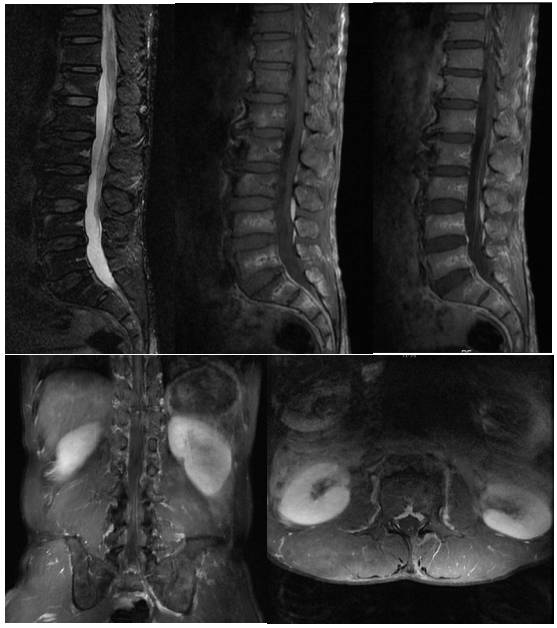

入院后查腰椎CT及腰椎增强MRI(图1)、(图2)。显示占位位于腰2椎体水平左侧腰1/2关节突内侧硬膜外,诊断首先考虑关节滑膜囊肿,囊性神经鞘瘤可能性较小。科室讨论,根据病灶位置及性质,拟行经皮脊柱内镜下探查,明确病灶性质,若术中探明属神经鞘瘤也可转显微开放手术。完善必要检查,与患者及家属沟通,知情同意后行脊柱内镜下经椎板间入路椎管探查+囊肿切除术。

图1. 腰椎增强MRI,腰2椎体水平椎管内占位,大小约18.8mmx16.9mmx30mm(左右x前后x上下)。病灶病灶类圆形,边界清晰,位于椎管左侧膜外间隙,边缘紧贴黄韧带,硬膜囊向右侧推压,相应马尾神经推压。病变上方马尾神经冗余、紊乱,提示椎管狭窄和神经受压。椎间孔未见扩大,邻近椎体后缘轻度受压吸收。T1和T2加权图像,病变核心液性信号,周边囊壁低信号。增强扫描,囊壁强化明显。

图2. 腰椎CT平扫,腰2椎体水平椎管内占位,病灶病灶类圆形,边界清晰,位于椎管左侧膜外间隙,病灶平均密度约15-20Hu。囊壁菲薄均匀。